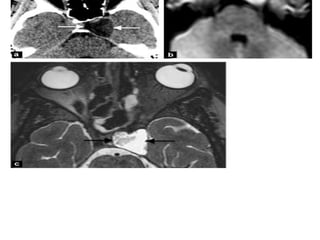

• #7 Aneurysm: axial T2-wi (a) shows a heterogeneous and enlarged right cavernous sinus with a multilayer appearance (black arrows) corresponding to a giant intracavernous aneurysm. Note the mass effect on the right temporal lobe. See also the 3D volume rendering showing the aneurysm (b).

• #10 Intracavernous aneurysms. A, Axial T2-weighted image shows a left intracavernous ICA (A) aneurysm. Note flow artifacts (arrow) confirming the pulsatile nature of the lesions. B, Coronal postcontrast maximum-intensity image from a CT angiogram in the same patient shows the left intracavernous aneurysm.

• #13 CS thrombosis. A, Coronal post contrast T1-weighted image shows an enlarged and inhomogeneous-appearing right CS that contains areas of low signal intensity (arrow) compatible with clot. B, Coronal post contrast T1-weighted image in a different patient shows a large nonenhancing clot expanding the left CS. The ipsilateral ICA is slightly narrowed.

• #14 Venous thrombosis: bilaterally heterogeneous and enlarged cavernous sinus on T2-wi (a), containing low signal areas on enhanced T1-wi suggesting clots (blacks arrows: b).